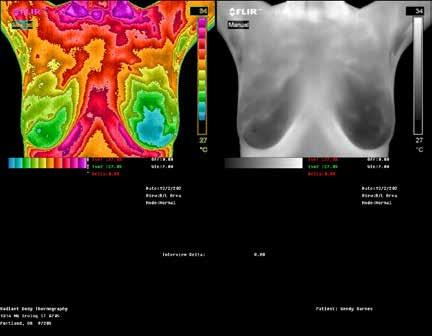

TOP: Thermographic pattern of physician-confirmed estrogen dominance, which the client addresses. BOTTOM: Images show success in removing the estrogen dominance pattern & client also downgrades her abnormal right breast! Estrogen dominance has a heat signature visible with QUALITY Thermography.